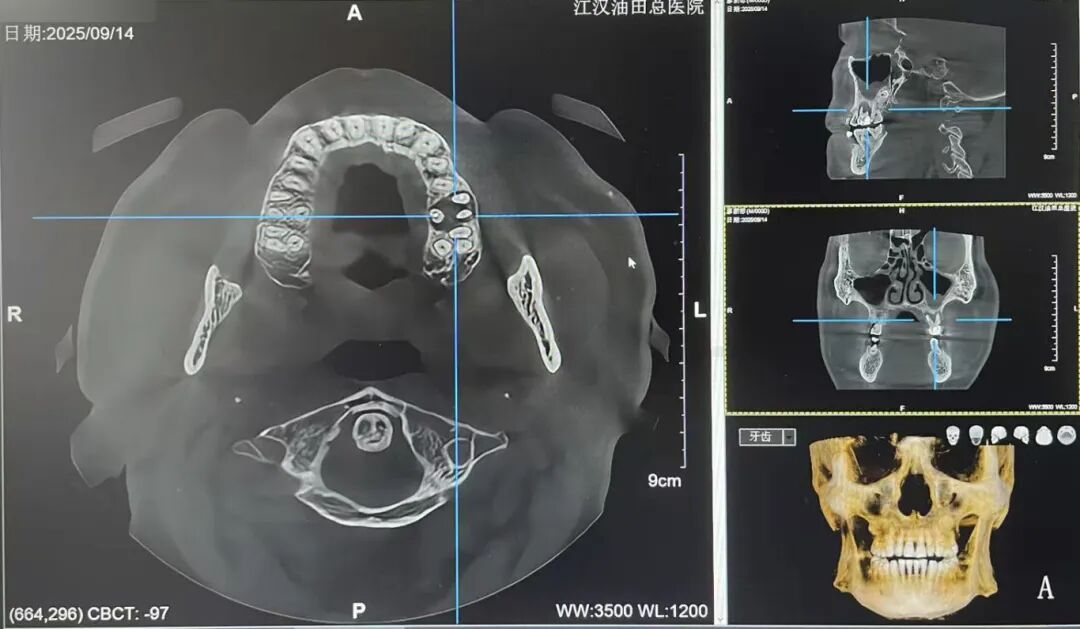

CBCT上线后,医生为他进行横断位、冠状位、矢状位全面扫描,逐层观察牙齿内部结构,终于在牙齿内部锁定病灶:根管有隐裂纹!

CBCT就像给口腔拍了一组“3D高清大片”,能清晰、直观地呈现口腔颌面部结构信息,为医生提供重要的诊断依据。

能清晰显示阻生智齿与神经管的关系。

能够精确地定位根管的形态、数目、走向,以及牙根尖的病变情况。

能精准测量牙槽骨密度,为种植牙“找准点位”。

通过AI多阶段重叠对比功能,可模拟牙齿移动轨迹。对于错颌畸形患者,CBCT颅颌面骨骼三维重建精确展现上下颌骨与颅底相对结构关系,为正畸医生制定治疗计划提供精确影像学数据,并还能提前预测生长发育趋势及矫治效果,有效减少复诊调整次数。